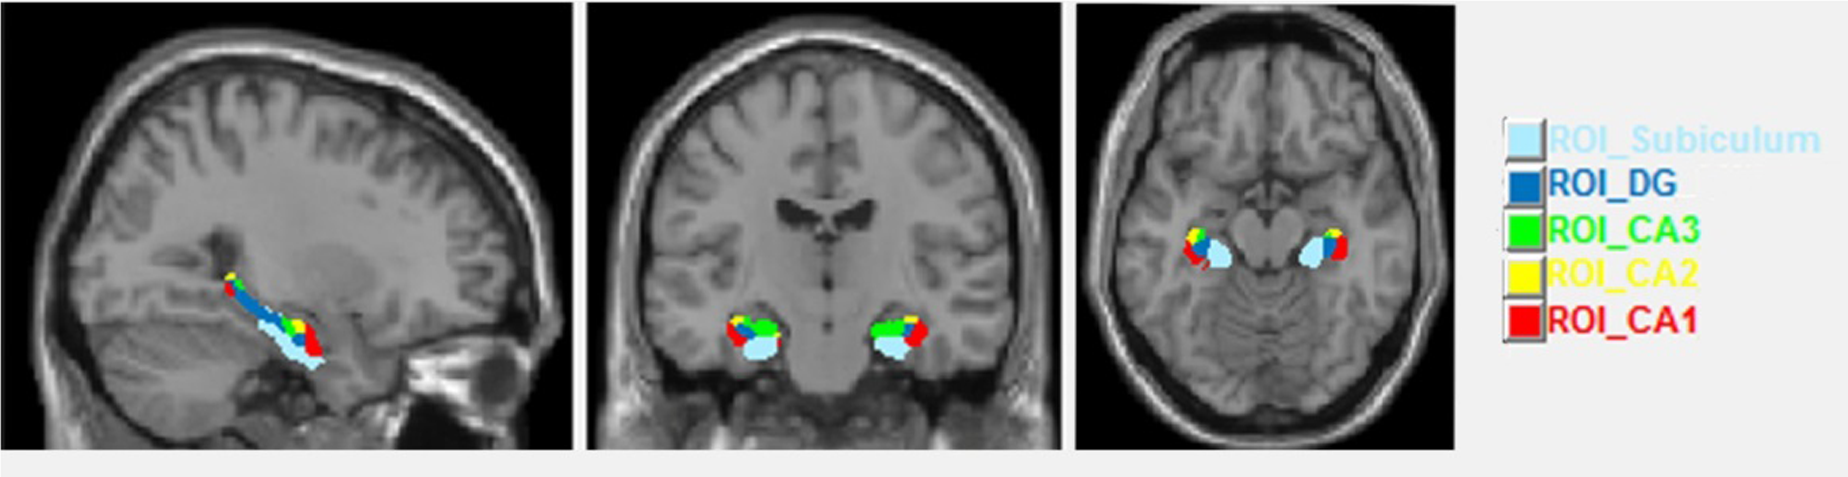

In a second step we analyzed volume changes in five subfields of the HC. Up to now there is no real gold standard in analyzing HC subfield volumes and each of the current manifold analytic techniques has its strengths and weaknesses (Bandettini, 2009; Kuhnt et al., 2013). Here for the hippocampal subfield segmentation in order to obtain ROI volumes we chose the SPM ANATOMY Toolbox v.2.2.c (Eickhoff et al., 2007) with normalized images. This segmentation included the cornu ammonis (CA1–CA3), the dentate gyrus (DG, including CA4) and the subiculum (Figure 2). In SPM Anatomy toolbox, definition of anatomical regions is based on maximum probability cytoarchitectonic maps.

FIGURE 2

Sagittal, coronal and axial views of the hippocampal subfields.